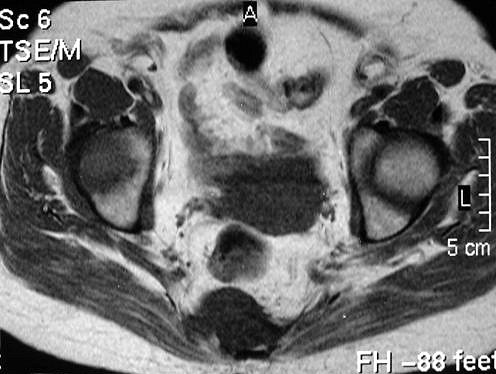

Сакральная хордома. Д-р Марсело Сенна Ксавье де Лима, Paul Roland Kaleff, и Антонио Рожерио del'Arco Roth Аугусто Варгас. Рецидив. Часть крестца была удалена ранее. Пнд, 27/11/2017 - 21:03 #1 Катенёв Валенти... Не на сайте Был на сайте: 7 лет 4 месяцев назад Зарегистрирован: 22.03.2008 - 22:15 Публикации: 54876 Внутричерепная хордома. http://pubs.rsna.org/doi/full/10.1148/rg.234025176 Пнд, 09/07/2018 - 20:44 #2 Катенёв Валенти... Не на сайте Был на сайте: 7 лет 4 месяцев назад Зарегистрирован: 22.03.2008 - 22:15 Публикации: 54876 Продолжение. Приложения: